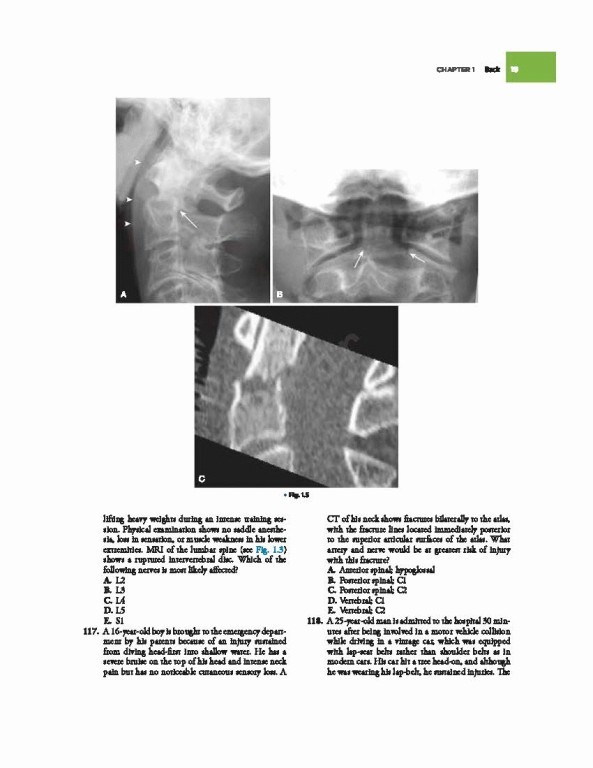

• 4 با تصاویر رادیوگرافی و سونوگرافی به‌روز شده

• Includes more than 1,400 high-yield questions, mirroring the USMLE Step 1 and complete with answers and rationales, that challenge your grasp of anatomical knowledge and the anatomical basis of disease.

• Helps you visualize key concepts with updated radiographic and ultrasound images and extensive use of photographs.